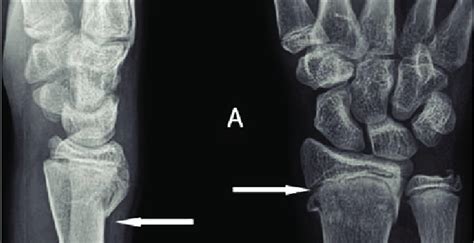

A buckle fracture, also known as a torus fracture, is a type of fracture that occurs in the wrist, typically in children. It is a common injury that occurs when a child falls onto an outstretched hand, causing the bone to bend and partially break. The fracture gets its name from the fact that the bone "buckles" or bends, rather than completely breaking. Buckle fractures are often seen in the distal radius, which is the bone in the forearm that connects to the wrist.

- Buckle fractures are often seen in the distal radius, which is the bone in the forearm that connects to the wrist.

The symptoms of a buckle fracture can vary depending on the severity of the injury. Common symptoms include pain, swelling, and limited mobility in the affected wrist. In some cases, the fracture may also cause numbness or tingling in the hand or fingers. To diagnose a buckle fracture, a doctor will typically perform a physical examination and take a medical history. They may also order imaging tests, such as X-rays or a CT scan, to confirm the diagnosis and assess the severity of the fracture.